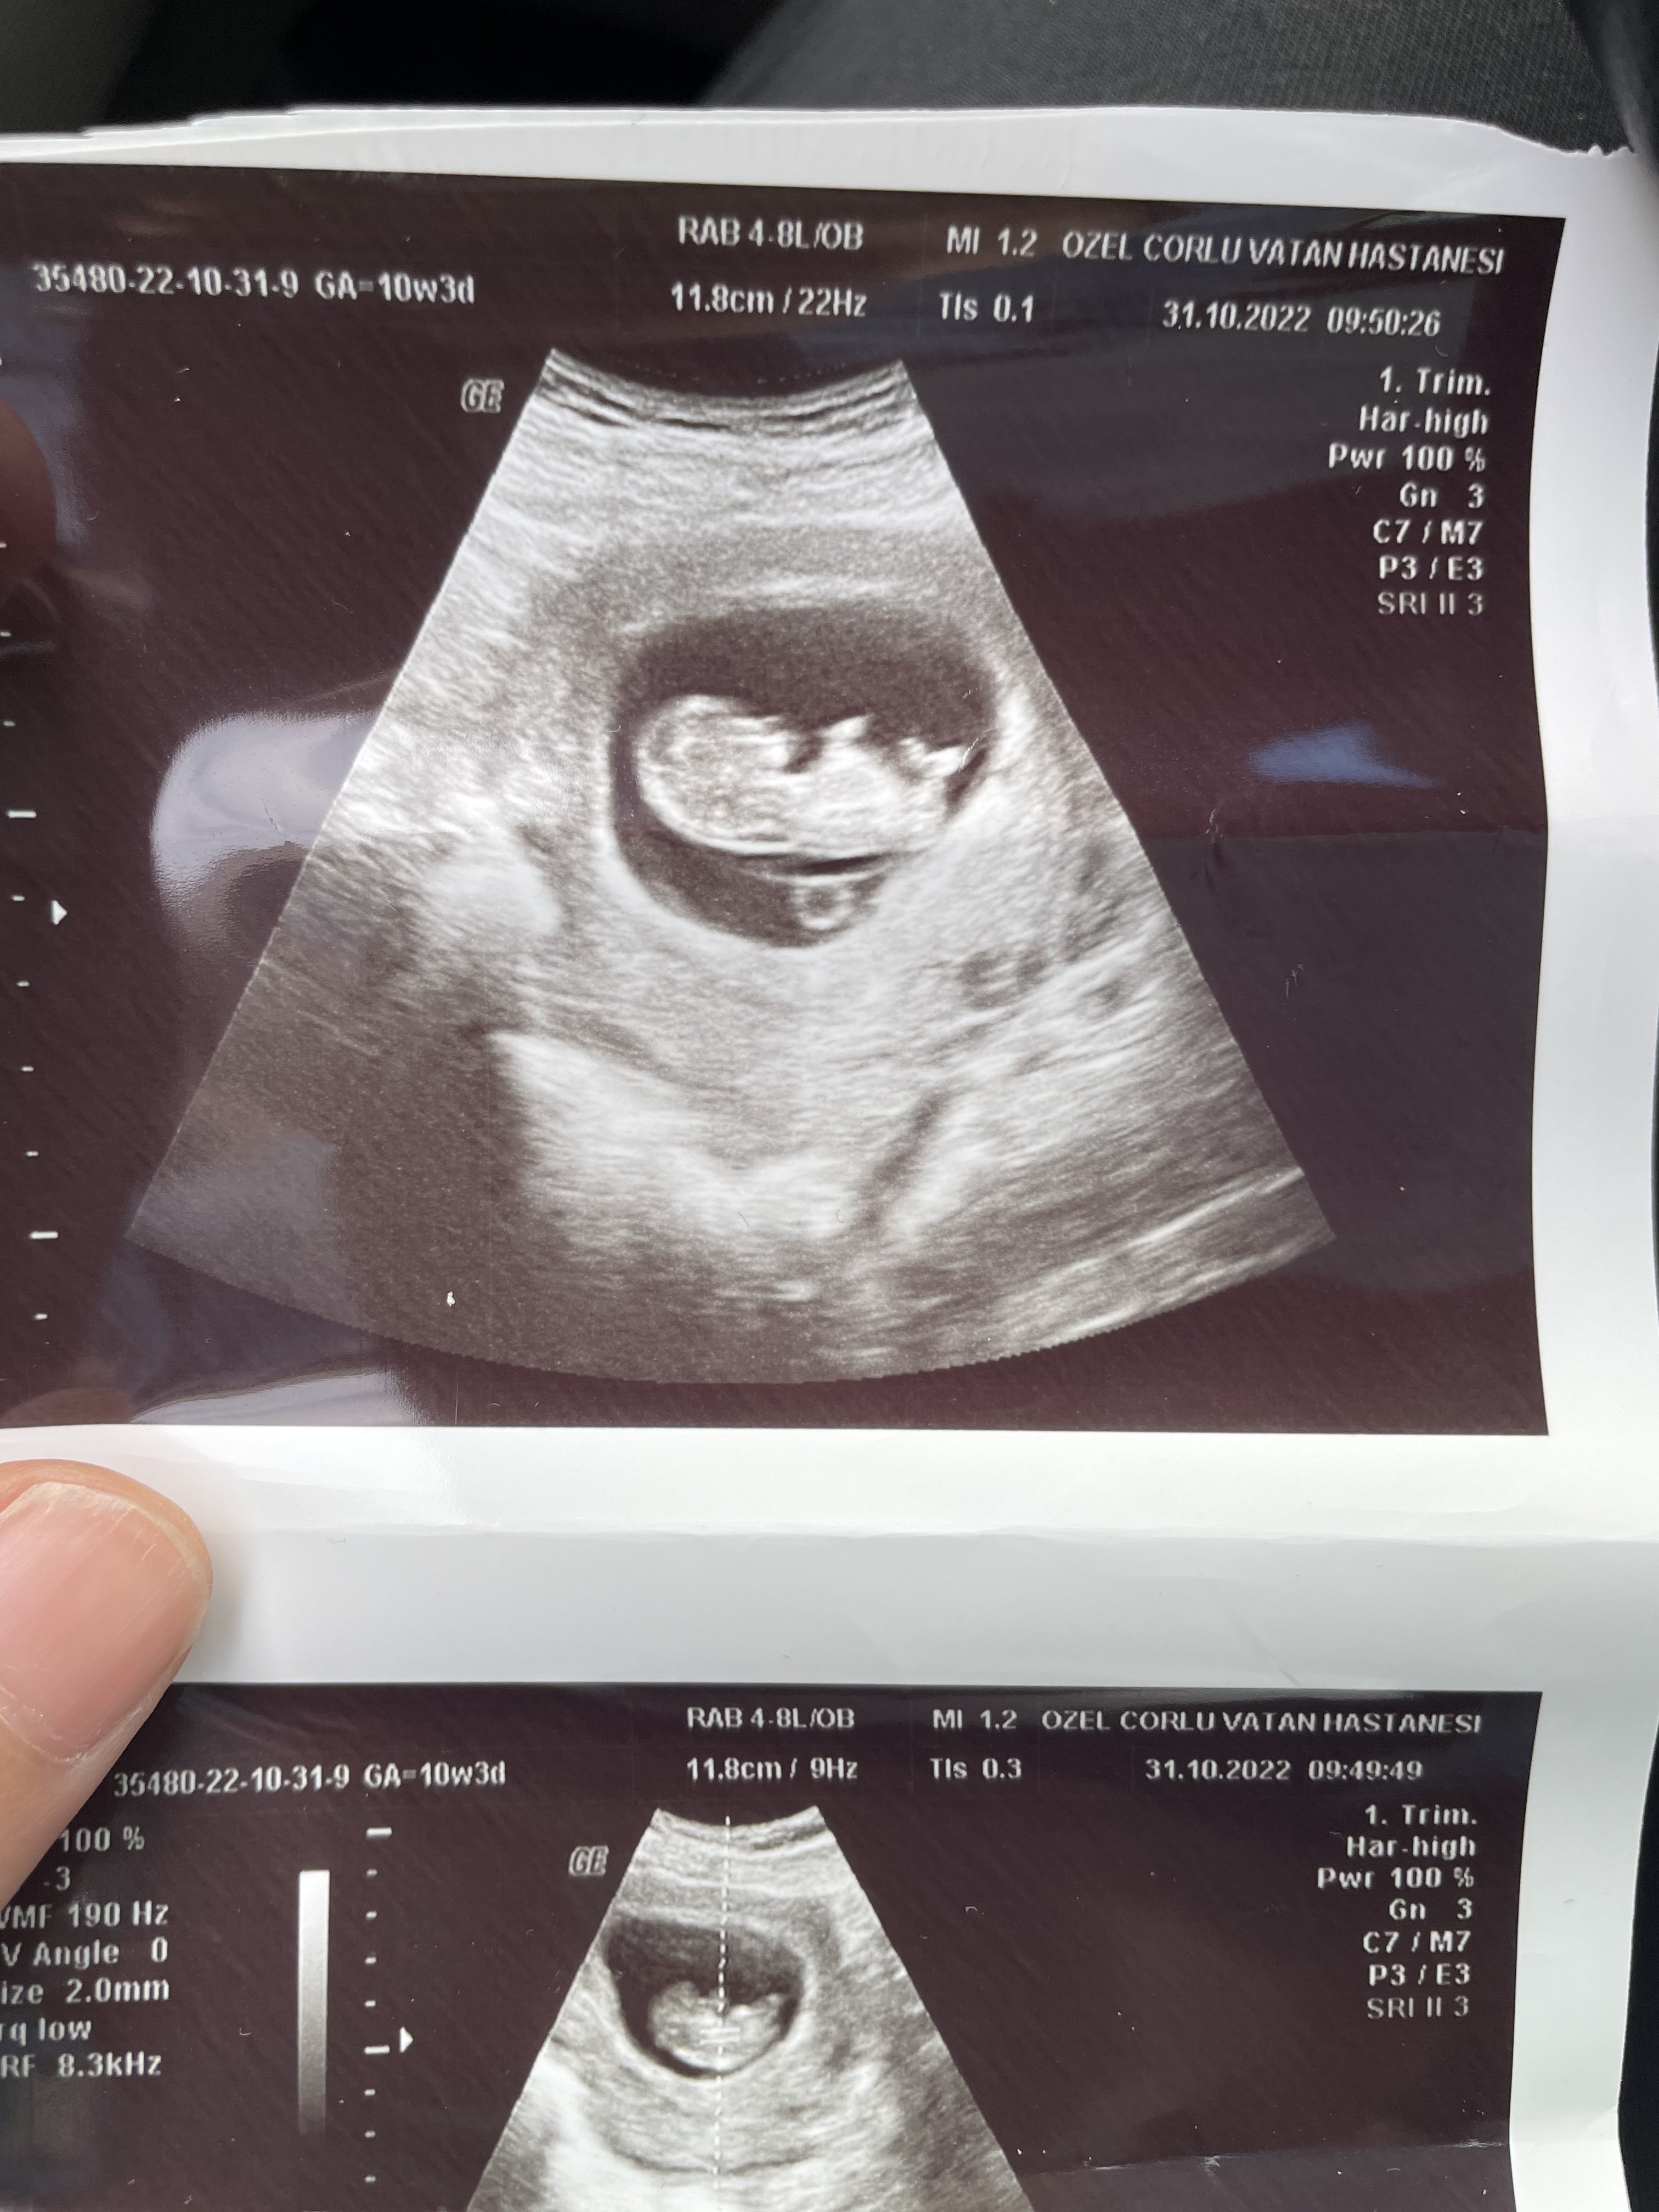

Selamlar ylzzz hayatım elinde başka resim var mı ? Var ise yükler misin lütfen.

Bu arada gözlerim beni yanıltmıyor ise yukarı doğru çıkıntı mevcut erkek gibi görüyorum ama çok net te değil hayatım. Tabi ki gaybı Allah bilir biz sadece bu olabilir diye söyleriz bilgin olsun 🙂 Yanılıyor olabilirim.

Malesef baska foto yok simdilik. Ama iki hafta sonra kontrolum var. O zaman tekrar rahatsiz edicem 🙂